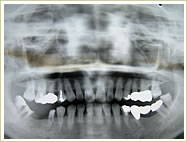

症例 65歳 男性 インプラント埋入数:11本 画像拡大

治療前 治療後